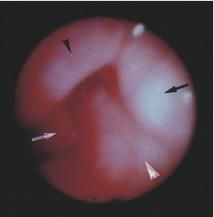

喉痛、聲嘶、喉喘鳴和呼吸困難,並可伴發熱惡寒,咽喉疼痛,喉鏡下可見黏膜呈深紅色水腫、表面發亮,喘鳴,聲嘶,呼吸困難,甚則窒息,喉鏡下可見喉黏膜瀰漫性水腫,蒼白。